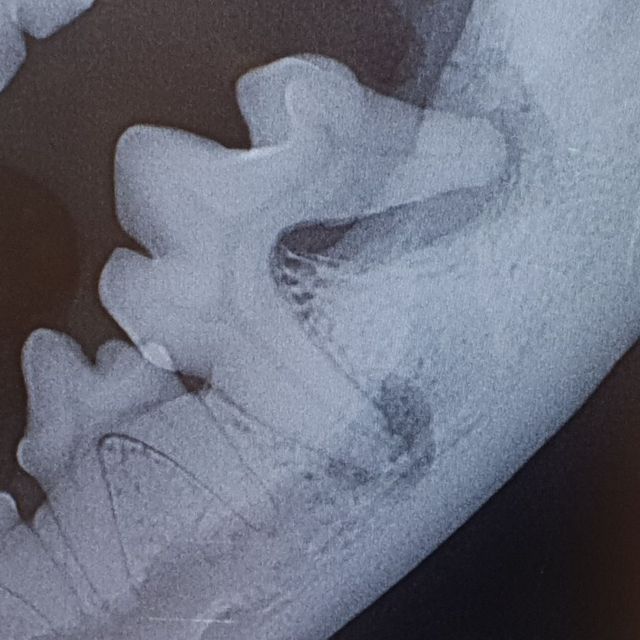

Etter hvert vil slik betennelse utvikle seg fra å være en overflatisk betennelse i tannkjøtt til en dypere betennelse mellom tanna og tannbeinet. Dette er svært smertefullt for dyret, og tanna vil løsne. I de fleste tilfeller vil den eneste løsningen for en slik tann være å trekke tanna. Dette vurderer dyrlegen din ved å gjøre en grundig undersøkelse av tanna og tannkjøttet, og ved å ta røntgenbilder av tanna. Dette må gjøres når dyret er i narkose.

Ved et tannrens hos oss blir først munnen skyllet med et antiseptisk middel. Deretter blir belegg og tannstein fjernet med ultralyd, før en fjerner tannstein under tannkjøttranden med en spesialskrape. Det er svært viktig at all tannstein - også den mellom og på baksiden av tennene fjernes. Deretter blir tanna polert glatt. Dette er viktig ettersom skraping av tannstein vil føre til riper i emaljen som bakterier og belegg vil få godt feste i om det ikke poleres bort. Så blir hver eneste tann undersøkt med en probe for å sjekke at det ikke er lommer i tannkjøttet eller problemer med røttene. Hos oss er også røntgenbilder av alle tennene inkludert i prisen for tannstell.

En tann som er brukket inn til pulpa, der nerven og blodkarene til tanna ligger, er svært smertefullt for hunden. Den blottede pulpaen vil også være inngangsport for bakterier, og vil ofte føre til tannrotsbyller. En slik skade kan i noen tilfeller repareres med rotfylling, dette må vurderes etter undersøkelse og røntgen av tanna. Dersom dette ikke er aktuelt må tanna trekkes.

Ofte er røntgenbilder den eneste måten å sikkert vurdere om en tann må gjøres noe med eller ikke. Hos oss er røntgenbilder av alle tennene inkludert i prisen ved tannrens.

Det er også viktig med røntgenbilder av aktuelle tenner både før og etter trekking, for å sjekke hvordan røttene ligger og ser ut - og for å kontrollere at en har fått med seg alt. Nødvendige røntgenbilder tatt i forbindelse med tanntekking blir det fakturert for.